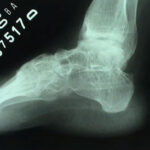

Hálux Rígido

O hálux rígido é uma patologia que afeta a articulação metatarsofalangeana do hálux, promovendo uma alteração degenerativa que leva à perda progressiva da mobilidade articular. Sua etiologia ainda não está totalmente definida, porém, pode estar relacionada a episódios de trauma, mas também pode estar associada a um primeiro metatarso elevado (verticalizado).

Os principais sinais e sintomas clínicos são dores na articulação metatarsofalangeana, perda progressiva da mobilidade e incapacidade ou dificuldade para usar salto, além de uma saliência dorsal. Existem vários níveis de gravidade, e o tratamento se baseia no aspecto clínico e radiográfico. Além disso, indicamos o tratamento conservador nos casos mais leves e em indivíduos com pouca perda da qualidade de vida. O tratamento cirúrgico pode variar de uma queilectomia (limpeza articular) aberta ou artroscópica as cirurgias mais complexas como osteotomias e artrodese (fusão articular).